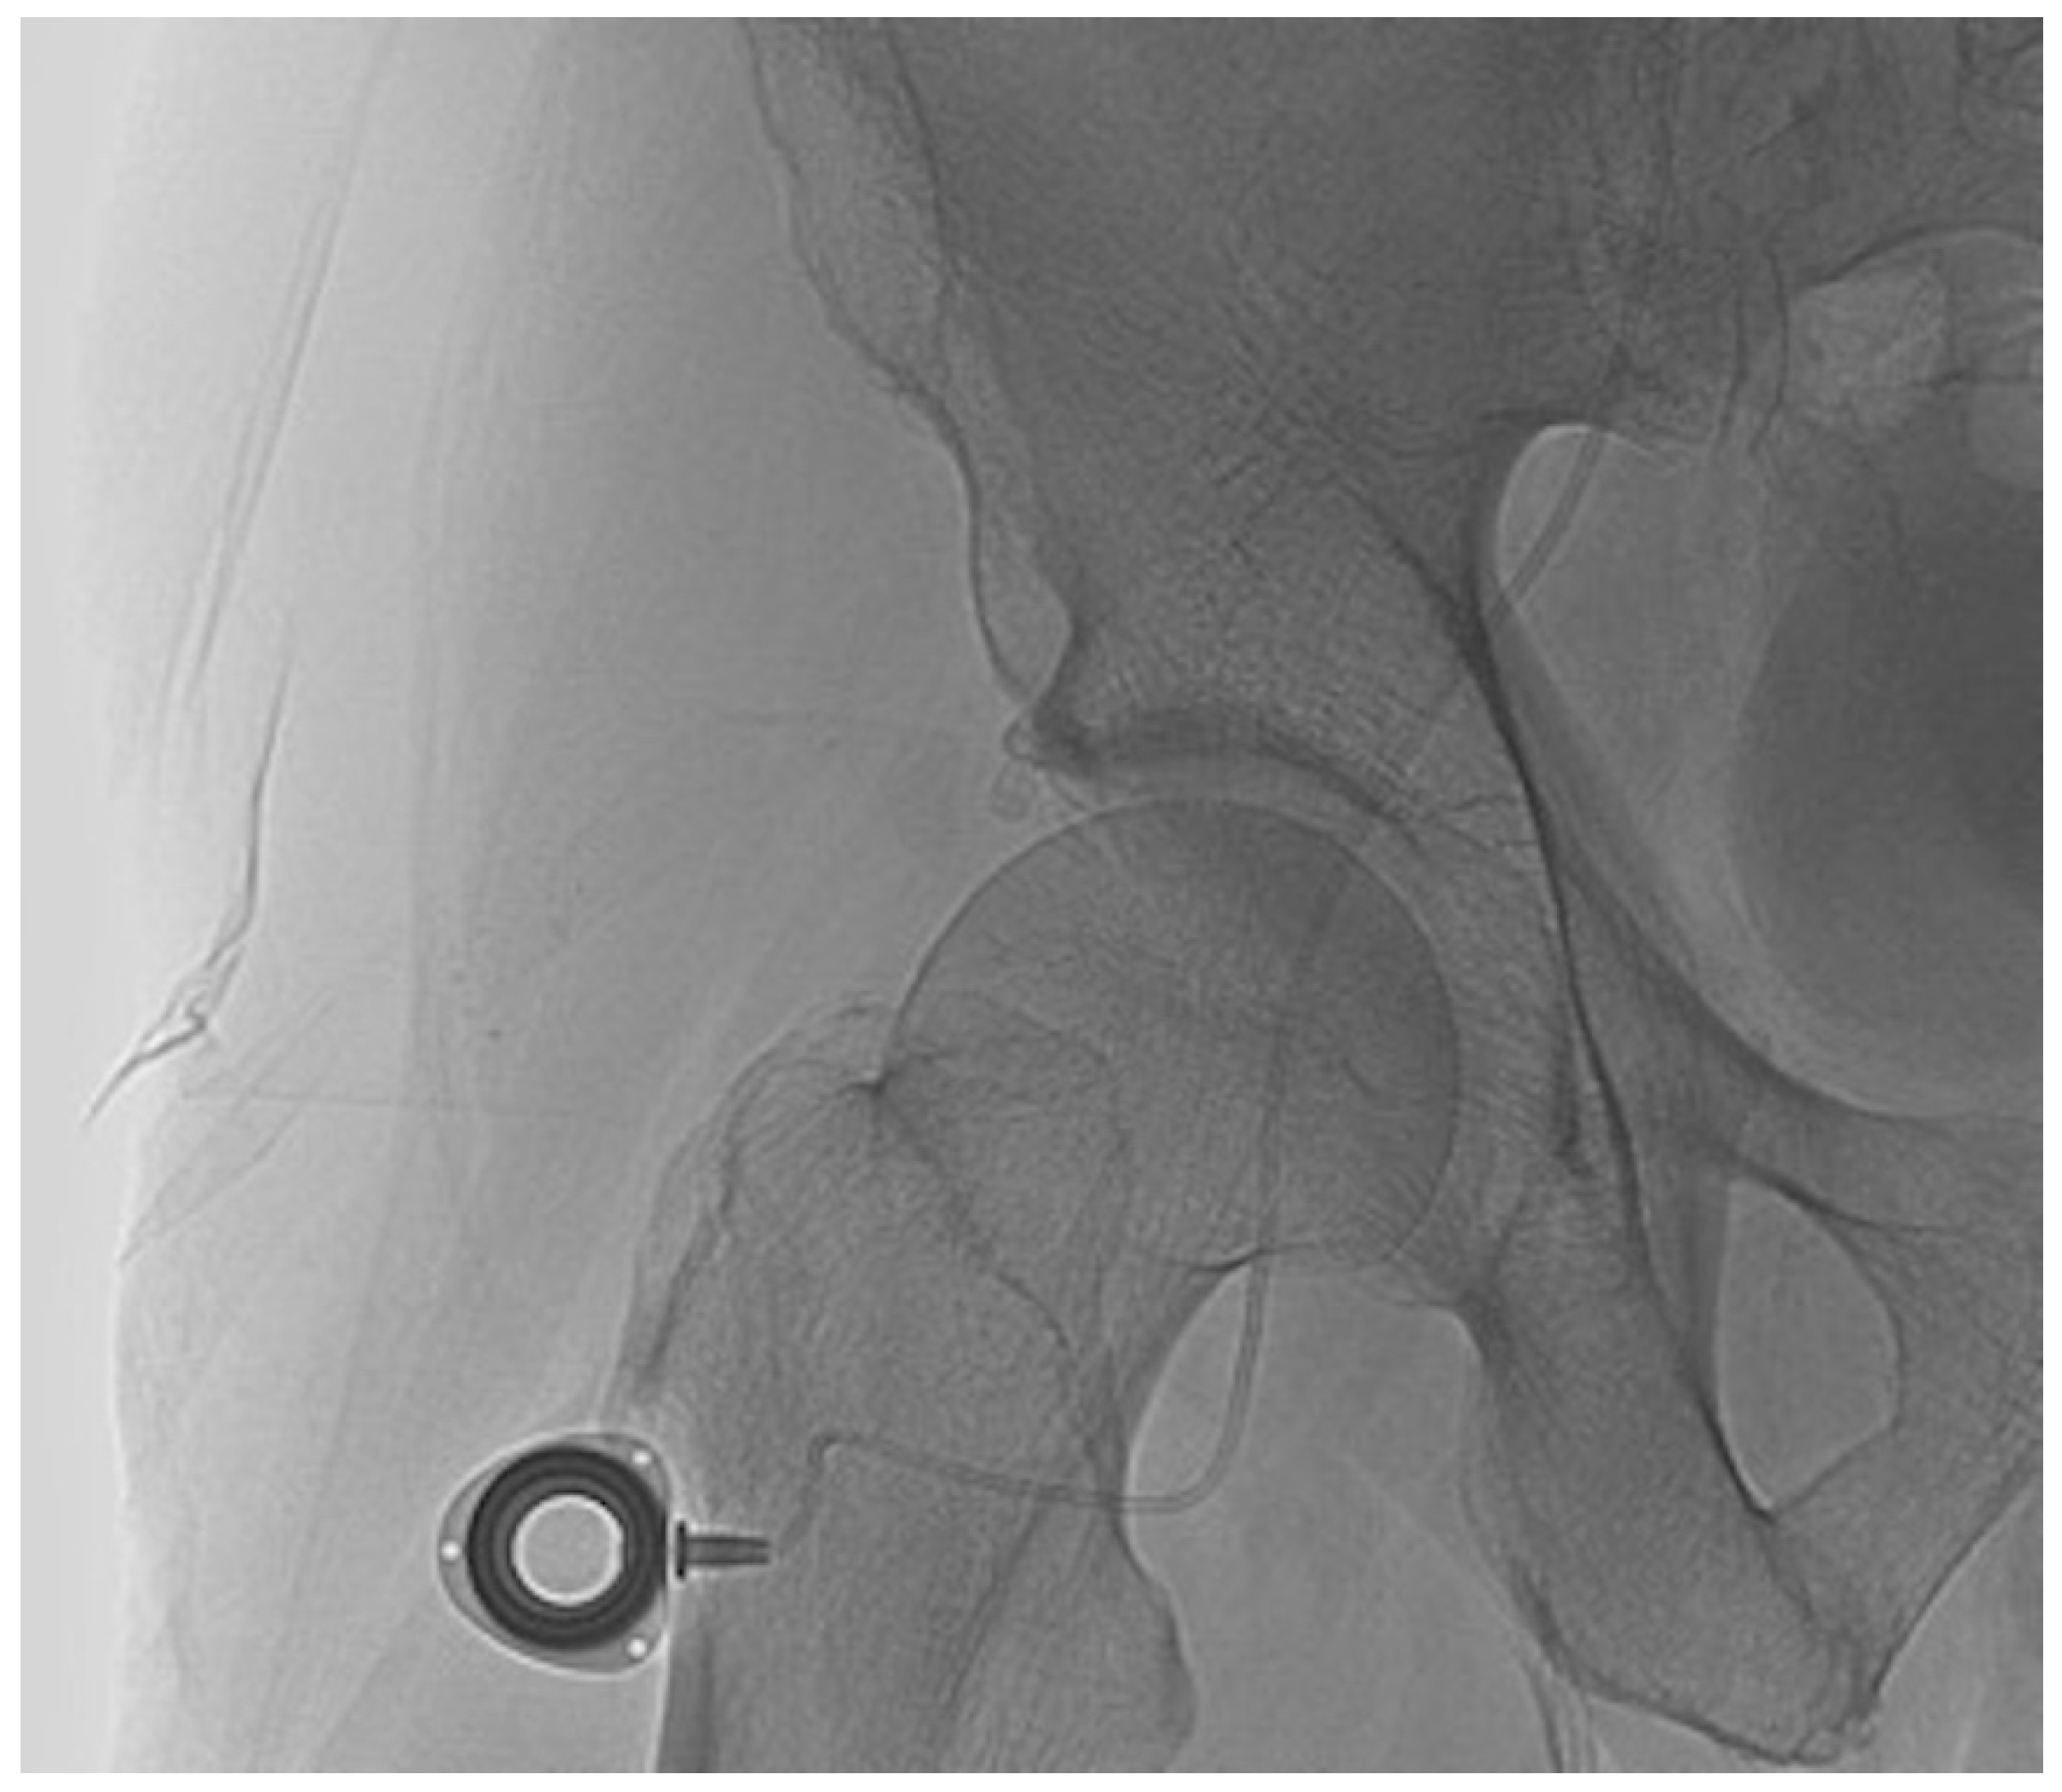

2.2. Percutaneous Microcatheter-Port System Implantation

3.2. Primary Technical Success